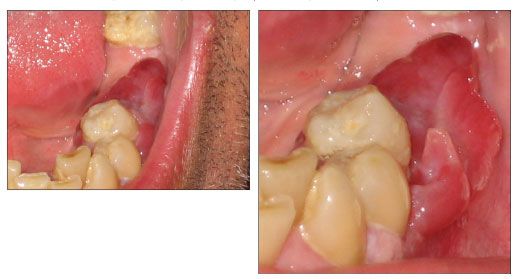

Figure 1.Reddish nodular mass extending across the alveolar ridge from the second premolar to the second molar, covering an edentulous area. The distention of buccal mucosa discloses the loss of attachment of the periodontal surface to the second premolar.

A previously healthy 43-year-old man was referred to the hospital for the diagnosis of a nodular lesion in the mandibular gingiva. The patient complained that his left lower jaw had been swelling over the past month, with some exudation from the gingival crevice, sporadic bleeding, and slight tooth mobility without pain. An intraoral examination revealed a reddish nodular mass (about 2 cm) that extended across the alveolar ridge from the second premolar to the second molar, covering an edentulous area, and the gingiva was detached from the second premolar by the mass (Figure 1). Palpation revealed soft tissue that seemed to arise in the periodontal ligaments.